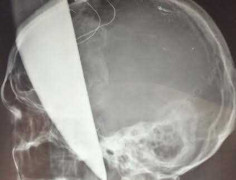

Do lưỡi dao nằm sát mạch máu lớn của não nên các bác sỹ phải dùng biện pháp mài vùng xương sọ quanh lưỡi dao để rút dao ra mà không làm đứt mạch máu não.